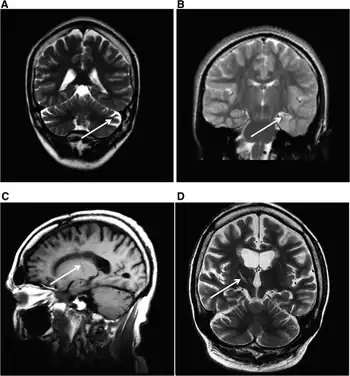

| MRI (adult) showing cerebellar atrophy in Dravet syndrome | |

The cause if often a genetic mutation in the SCN1A gene.[4] Around 90% of mutations newly occur during early development, rather then being inherited from a person's parents.[3] A family history of seizures is present in nearly half of cases.[8] Diagnosis is based on symptoms and genetic testing.[5] MRI of the brain is typically normal initially, though may show changes such as atrophy in some adults.[2]